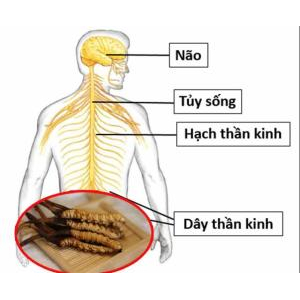

- Kích thích sản xuất nhiều hormone Adrenalin hơn. Đây là một loại hormone có chức năng vận chuyển oxy tới não bộ và nhiều cơ quan khác trong cơ thể.